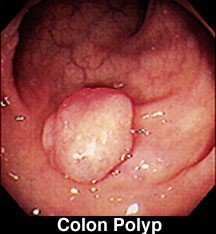

• Kolonoskopiyada polip

yob img 23

yob img 24

Şəkil 1. Yoğun bağırsaq poliplərində ikimərhələli “çıxart bax” yanaşması